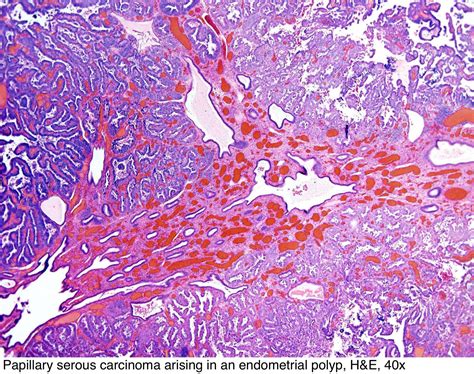

Receiving a diagnosis of Papillary Serous Carcinoma can be an overwhelming and life-altering experience. As a subtype of epithelial cancer that most commonly originates in the ovaries, fallopian tubes, or the peritoneum, it is characterized by its distinct cellular structure under a microscope, where the cells form small, finger-like projections known as papillae. Understanding the nature of this malignancy is the first step toward navigating treatment options, communicating with your medical team, and advocating for your own health journey. By breaking down the complexities of this condition, patients and caregivers can better grasp the diagnostic processes, treatment pathways, and the ongoing support structures available.

At its core, Papillary Serous Carcinoma is considered an aggressive form of cancer because it often presents at a later stage. Because the symptoms are frequently subtle—or even non-existent—in the early phases, the disease often spreads throughout the abdominal cavity before it is detected. The term "serous" refers to the fluid-producing cells from which the tumor arises, and "papillary" describes the architectural pattern of the cells.

While often associated with ovarian cancer, it is essential to distinguish between localized disease and primary peritoneal carcinoma. In many modern clinical settings, these are treated with similar protocols because the underlying biological behavior of the malignant cells is remarkably similar. Key characteristics of this cancer include:

• High-Grade Classification: Most cases are categorized as high-grade, meaning the cells look significantly different from normal cells.